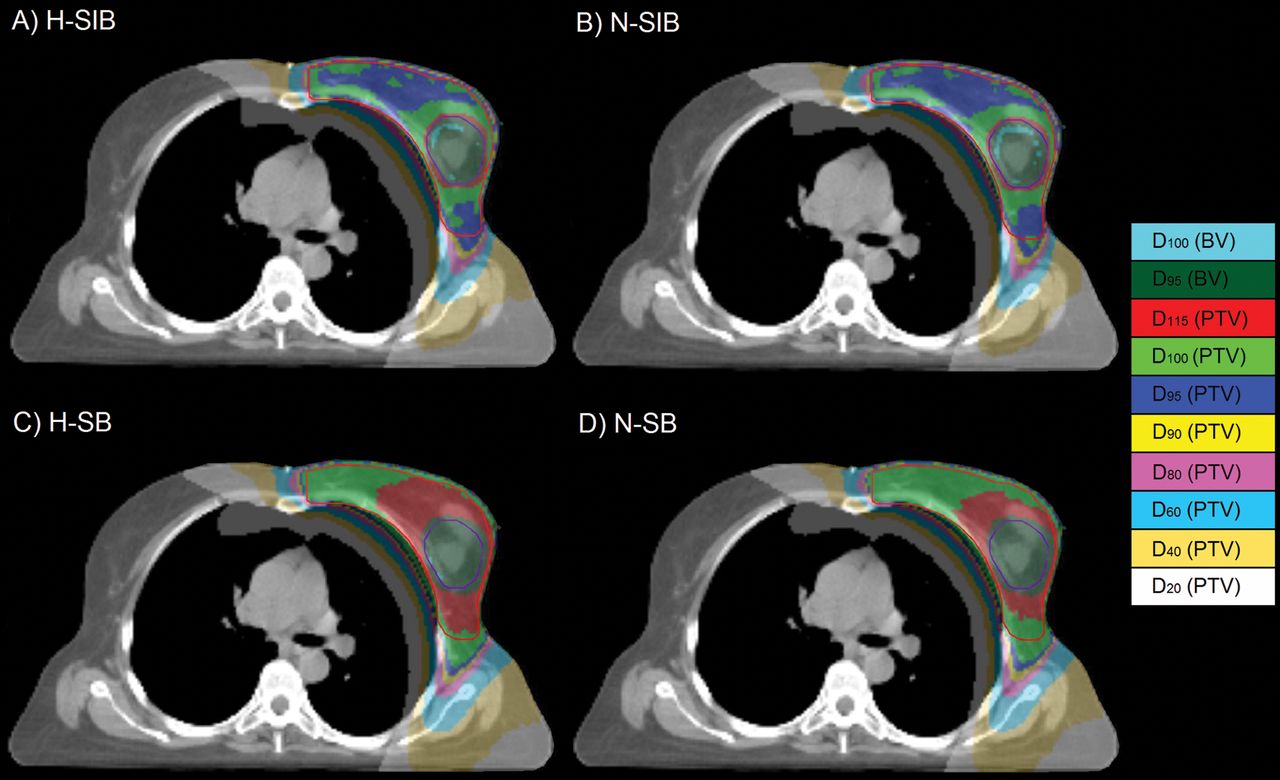

Pegah Saadatmand11Medical Physics Department, Iran University of Medical Sciences, Iran Abstract Introduction: Radiation-induced acute skin toxicity (AST), is considered a common side effect of breast radiation therapy. The goal of… more